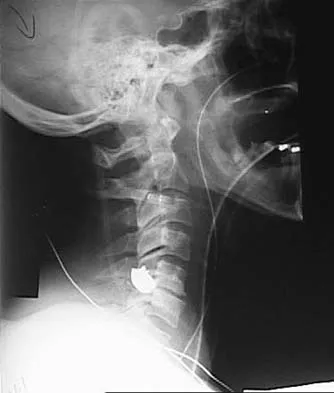

A 28-year-old professional dancer reports a 3-month history of progressive pain in the posterior aspect of the left ankle. Her symptoms are worse when she assumes the en pointe position. Examination reveals tenderness to palpation at the posterolateral aspect of the ankle posterior to the peroneal tendons which is made worse with passive plantar flexion. There is no nodularity, fluctuance, or tenderness of the Achilles tendon. The neurovascular examination is unremarkable. A lateral radiograph and MRI scan are shown in Figures 16a and 16b, respectively. Management should consist of

The imaging studies reveal findings typical of the os trigonum syndrome. This condition results from inflammation between the os trigonum and the adjacent talus. The symptoms of posterior ankle pain are exacerbated by plantar flexion, which stresses the fibrous union between these two bones. Definitive management of the high-level athlete involves excision of the os trigonum from a medial approach, although arthroscopic excision has also been described. The os trigonum is not an intra-articular structure; therefore, ankle arthroscopy is neither diagnostic nor therapeutic. Abramowitz Y, Wollstein R, Barzilay Y, et al: Outcome of resection of a symptomatic os trigonum. J Bone Joint Surg Am 2003;85:1051-1057. Mouhsine E, Crevoisier X, Leyvraz P, et al: Post-traumatic overload or acute syndrome of the os trigonum: A possible cause of posterior ankle impingement. Knee Surg Sports Traumatol Arthrosc 2004;12:250-253.